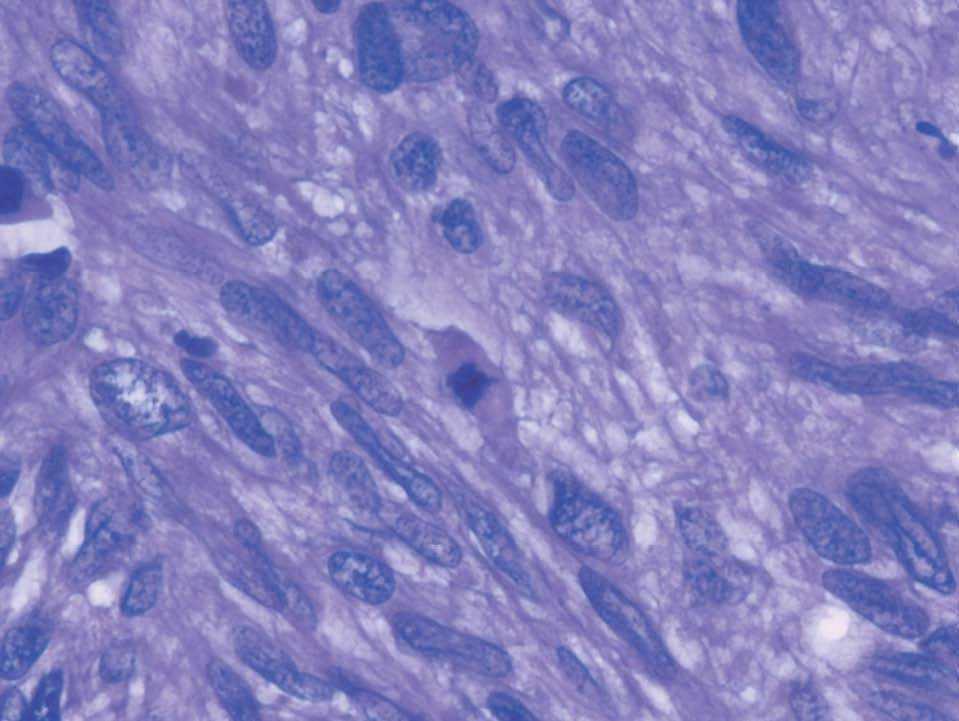

Histológicamente, la tumoración estaba constituida por células de morfología fusiforme, citoplasma eosinófilo, con un patrón fibrilar de límites imprecisos, y núcleos elongados con bordes romos y cromatina fina (fig. 2). No había necrosis tumoral ni patrón infiltrativo en los márgenes tumorales. Tampoco se observaban áreas mixoides, y la celularidad mostraba una atipia nuclear de forma focal en algunas áreas, aunque sin adquirir un grado pleomórfico (fig. 3). Según las áreas, había abundantes figuras mitóticas que oscilaban, en los distintos recuentos realizados, entre 5 y 7 mitosis por cada 10 campos de gran aumento. El estudio inmunohistoquímico realizado mostró una intensa positividad para vimentina, actina músculo liso (fig. 4) y desmina, así como para los receptores de estrógenos y la progesterona; las queratinas y la proteína S-100 fueron negativas.

Figura 3. Núcleos alongados, irregulares con cromatina gruesa y figuras mitóticas (HE, ×40).